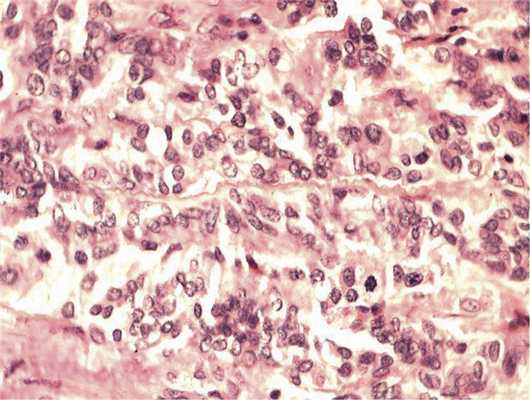

Отмечалось наличие ленточных структур из низкодифференцированных эпителиальных клеток (рис. 4). Параллельно встречались участки солидного строения из клеток с гиперхромными ядрами с признаками клеточного и ядерного полиморфизма. В них почти исчезает строма, появляются митозы, встречаются участки дистрофии и некроза (рис. 5). Опухоль врастает в ткань ДЗН с переходом за laminacribrosa, но не достигает линии отсечения (рис. 6). В таком виде опухоль обладает местнодеструирующим характером роста и может давать метастазы, глубоко инфильтрируя прилежащую к ДЗН ткань хориоидеи. Окончательный гистологический диагноз: злокачественная медуллоэпителиома центрального отдела сетчатки с вовлечением ДЗН и инвазией перипапиллярной хориоидеи, с глубоким прорастанием по зрительному нерву, не достигая линии отсечения.

Рис. 4. Формирование полос из низкодифференцированных нейроэпителиальных клеток. Окраска гематоксилином и эозином. Ув. 400.

Рис. 5. Зоны солидного роста опухоли. Клеточный полиморфизм с фигурами митозов. Окраска гематоксилином и эозином. Ув. 400.